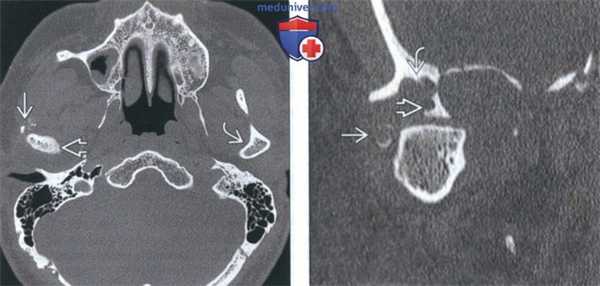

(Слева) На аксиальной КТ в костном окне визуализируется большая агрессивная остеосаркома со стороны наружного края ветви нижней челюсти. Определяется лучистая периостальная реакция, виден остеоидный матрикс.

(Справа) На корональной КТ в костном окне у этого же пациента определяется лучистая периостальная реакция со стороны внутреннего и наружного края ветви с «пятнистой» деструкцией и увеличением мыщелка.